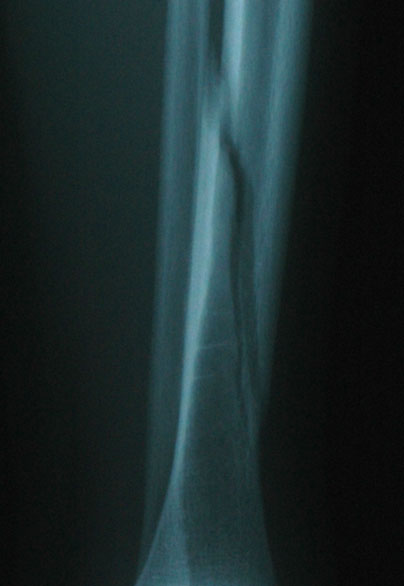

A week later, and the gap has closed up a bit: